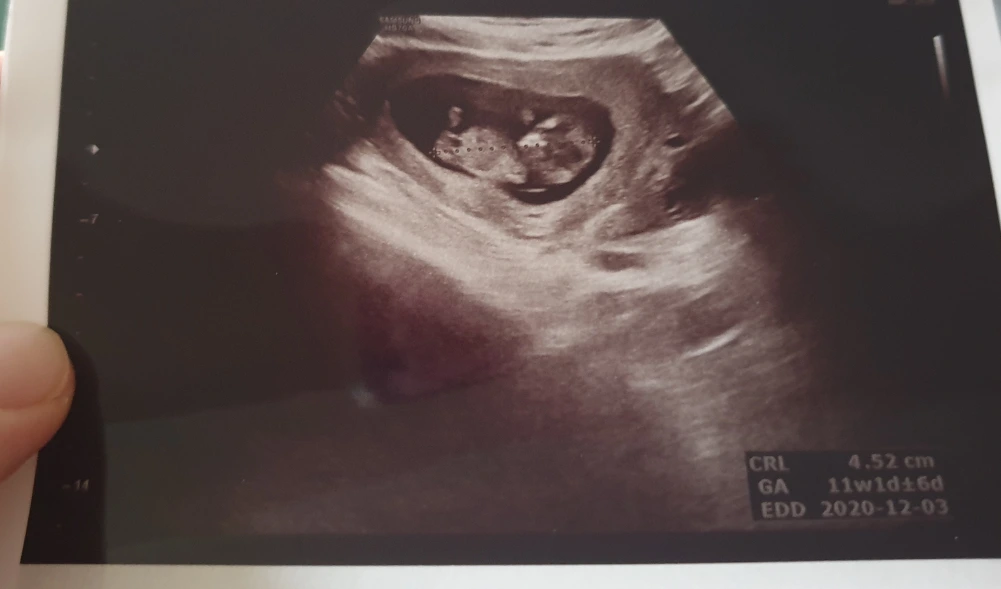

그리고 이 때 초음파로 '목투명대검사'도 한다. 목투명대는 태아의 목덜미 뒤 목투명대 두께를 재는 검사인데, 측정했을 때 두께가 2.5mm이상이면 염색체 이상이 있을 확률이 높다. 다행히 우리 아기는 0.8mm! 정상이라고 하셔서 기분이 너무 좋았다. 그 외에도 걱정할 만한 요소없이 아이는 무럭무럭 잘 자라고 있었다.

처음에는 형체도 없던 아이가 이젠 흔히 말하는 '젤리곰' 형태로 변한 걸 보고 정말 신기해서 남편과 몇번이나 초음파 사진을 봤는 지 모르겠다.